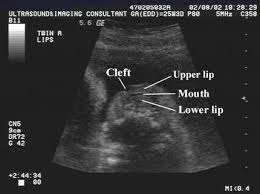

I may just be being paranoid bc i am a very paranoid person anyway. Involve the superficial tissues. Cleft lip may be detected with ultrasound beginning around the 13th week of pregnancy. Best seen on coronal images of the upper lip.

Best seen on coronal images of the upper lip. Type 2 unilateral. My ultrasound tech said that she can easily spot a cleft lip but a cleft palate is much harder to see i am sure you could google ultrasound pics with cleft lips and see some pictures. An explanation why the cleft was mistakenly considered to be one on the left side could be that the cleft was located near to the midline and the 2d ultrasound frontal view was an oblique frontal view figure 1.

Midline sagittal views normal. Ultrasound pic looks like cleft lip and im freaking out. Ultrasound of cleft lip and palate. What does cleft lip look like in ultrasound i think you can see it easily especially the 3d 4d one.